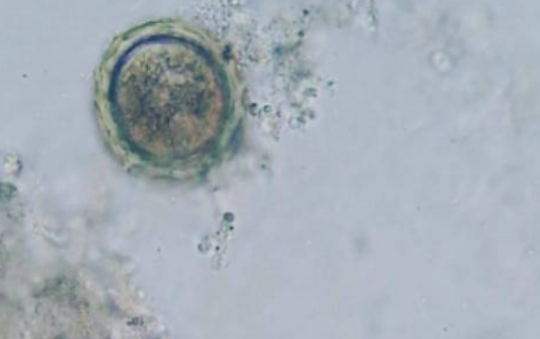

Que podemos observar en el microscopio óptico: podemos observar bacterias, parásitos, hongos, células sanguíneas, cristales en orina, entre otros.

Ejemplo:

Parásito: Ascaris lumbricoides a objetivo de 40 X con microscopio óptico. Foto propiedad del autor/@osita21